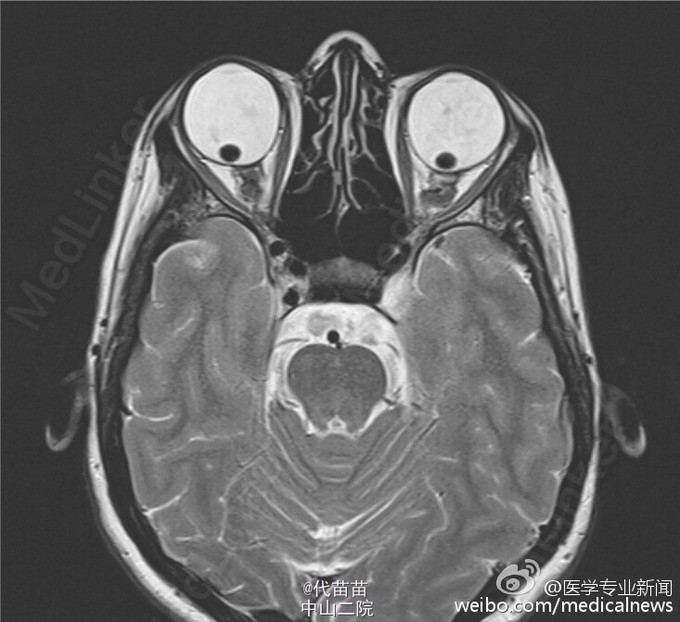

31岁女性马方氏综合征患者,因弱视入院,过去3~4个月期间逐渐出现双眼视力下降,并在过去2周内出现中度感觉神经性听力损失。眼科检查发现蓝色巩膜和视力严重下降。右眼最佳矫正视力20/80,左眼20/400。双侧扩瞳后的裂隙灯检查可见晶状体与玻璃体脱位。此外可见视网膜变性,但未见视网膜裂孔或剥离。眼内压正常。由于患者存在不明原因的听力下降,因此进行MRI检查,T2加权下的眼眶轴向平面图像可见双眼晶状体后脱位。马方氏综合征是一种影响结缔组织的常染色体显性遗传病。这些患者常见包括晶状体脱位在内的眼部病变。该患者拒绝接受眼科手术治疗,并接受矫正眼镜保守治疗。听力下降被认为与病毒感染有关。给予类固醇后听力完全恢复。随访2年期间,患者的视力下降程度稳定,期间并未出现恶化。转自 新浪微博@医学专业新闻